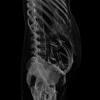

Dr. Lazarus and colleagues conducted a retrospective review of nuclear medicine, CT, fluoroscopy and plain-film X-ray imaging examinations performed at Rhode Island Hospital and Women and Infants’ Hospital from 1997 through 2006 to determine how often these imaging exams were performed on pregnant women and the estimated radiation dose to the fetus. Data were then compared to the number of infant deliveries per year for that same time period.

CT exams are not routinely ordered for pregnant women, but may be necessary to detect suspected life-threatening conditions such as bleeding in the brain, blood clots in the lungs or appendicitis. Since CT exposes the developing fetus to radiation, concerns are often raised regarding overuse. The majority of CT examinations (approximately 75 percent) analyzed in the study were performed in areas of the mother’s body separate from the uterus, so the fetus was not exposed to any direct radiation. Still, low levels of radiation have been shown to carry a small risk of harm to a developing fetus.

A milliGray (mGy) is a unit of measure for absorbed radiation. The average estimated fetal radiation exposure per exam for CT was 4.3 mGy, compared to 2.91 mGy for fluoroscopy, 0.40 mGy for nuclear medicine and 0.43 mGy for x-rays.